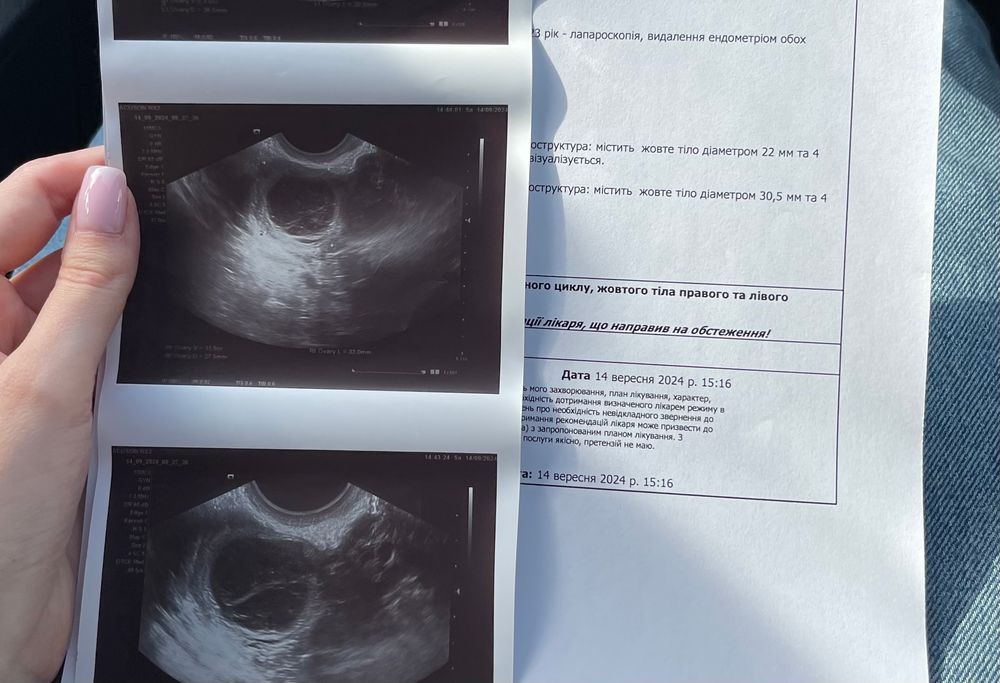

двойная овуляция ✨

Д, пока нет 😹 дай Бог, чтоб хоть одна яйцеклетка нашла дорогу, с моими то спайками )) но шансы в этом цикле есть 😁